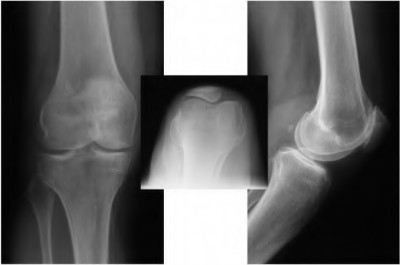

A 55-year-old male presents with isolated medial compartment osteoarthritis of the right knee. He is being evaluated for a medial unicompartmental knee arthroplasty (UKA). Which of the following physical examination or radiographic findings is an absolute contraindication to a medial UKA?

When planning a medial opening wedge high tibial osteotomy (HTO) for isolated medial compartment osteoarthritis in a varus knee, the surgeon intends to shift the mechanical axis to the Fujisawa point. Where is the Fujisawa point located on the tibial plateau?